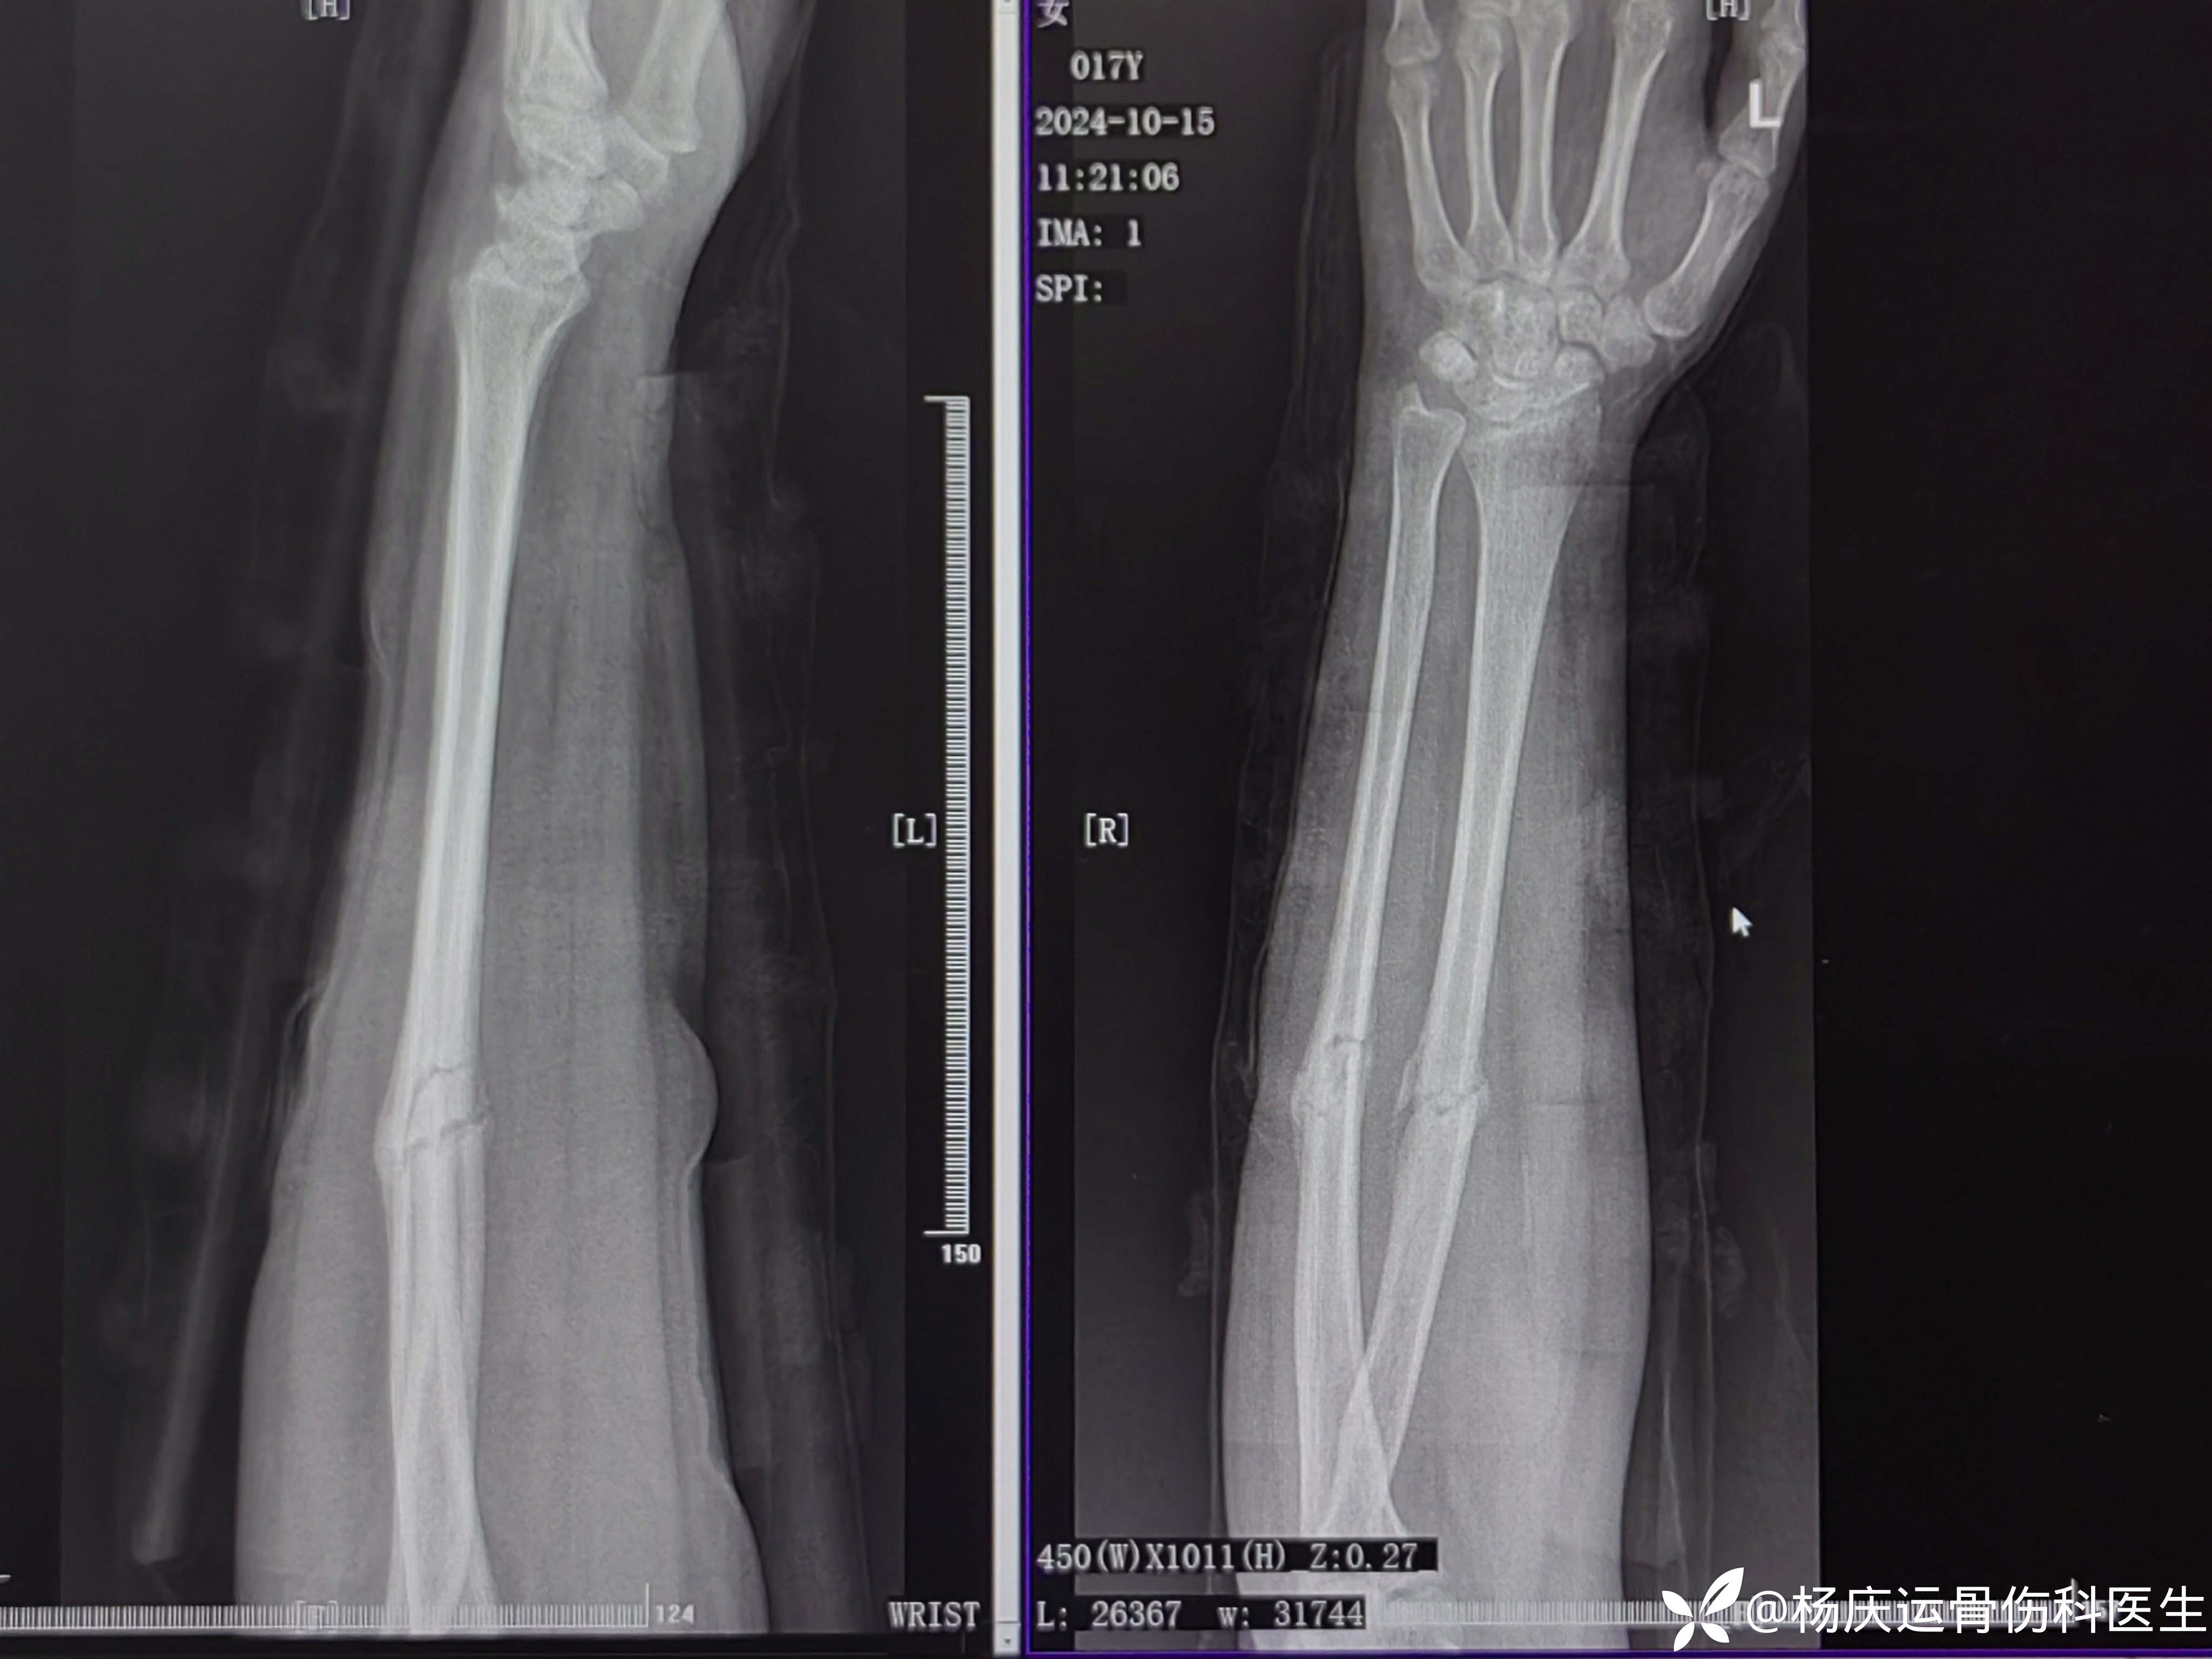

患者李,女,17岁,左前臂外伤肿痛11天。

外院要求手术治疗,转来诊。

初步诊断:左尺桡骨骨折

自带首诊片

11天拍片复查